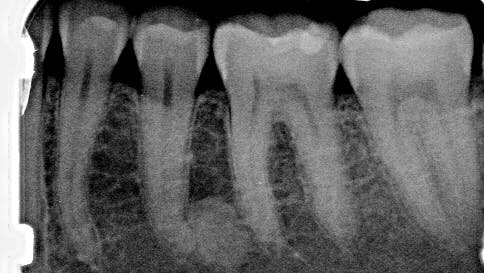

A healthy 41-year-old female presented to the office for a routine exam and checkup. Her health history was normal, and she reported no major concerns or issues.

Radiographic examination revealed a large, radiopaque mass just distal to the apical third of tooth no. 20. The area was not tender to palpation, and the tooth tested vital and WNL.

Periapical idiopathic osteosclerosis

The lack of radiolucent border and the unknown etiology of the lesion strongly indicate that this lesion is periapical idiopathic osteosclerosis. Since there are no previous radiographs to reference, this diagnosis is not concrete. This diagnosis presents no clinical significance; hence, the patient will be reexamined periodically. Any changes and subsequent treatment will be rendered.